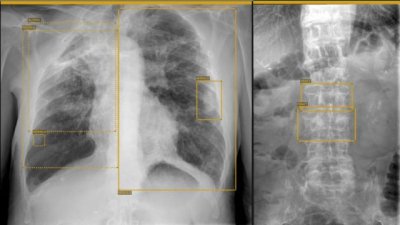

Esta solución permitirá valorar las lesiones óseas traumáticas y tumorales así como patologías en el entorno de la ortopedia y…